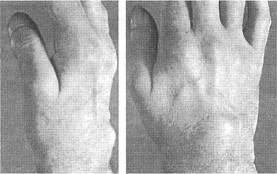

Обычно ревматоидный артрит начинается с симметричного полиартрита периферических суставов (рис.1), что проявляется их припухлостью, болезненностью и скованностью, причем последняя может поражать большее количество суставов, чем первые два симптома. Характерным для ревматоидного артрита является вовлечение проксимальных межфаланговых, пястно-фаланговых суставов и лучезапястных суставов кистей. Дистальные межфаланговые суставы, пястно-фаланговый сустав I пальца и проксимальный межфаланговый сустав V пальца кисти считаются "суставами исключения" так как в большинстве случаев остаются интактными в дебюте болезни, однако могут вовлекаться в процесс при прогрессировании ревматоидного артрита.

Припухлость пястно-фаланговых и проксимальных межфаланговых суставов кисти с веретенообразной де фигурацией последних, ассоциирующаяся с утренней скованностью, затруднением сжатия кисти в кулак, снижением кистевой силы и болезненностью при пальпации (см. рис.1).

Рис.1. Кисты больного с ранним ревматоидным артритом